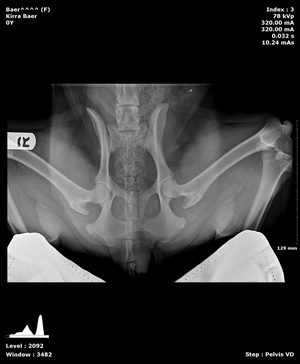

Pennhip X-rays in Williamsfield & Elmwood, IL

Wags and Whiskers is one of the few facilities in the state that offers PennHip diagnostics. PennHipp is a tool used to measure hip laxity. It can detect the presence of osteoarthritis or hip dysplasia in canine companions. Breeders often use this service to determine breeding soundness. It can be performed on patients as young as 16 weeks old.